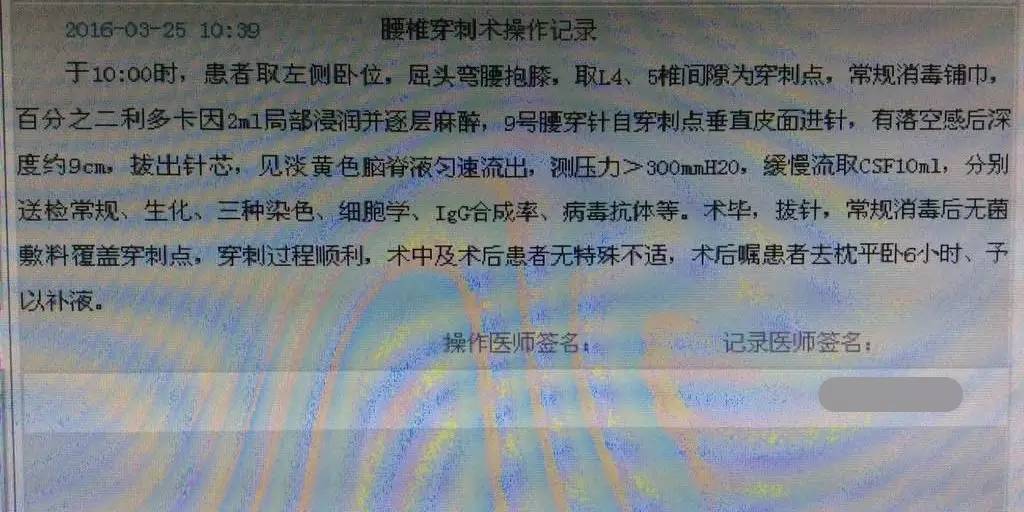

2016-3-25腰穿压力>300mmH2O,细胞计数80×106/L,脑脊液蛋白5.432g/L,葡萄糖0.03mmol/L,氯化物112.3mmol/L,脑脊液IgG601mg/L。脑脊液墨汁染色(-),抗酸染色(-),间皮细胞30%,单核细胞30%,多核细胞40%。